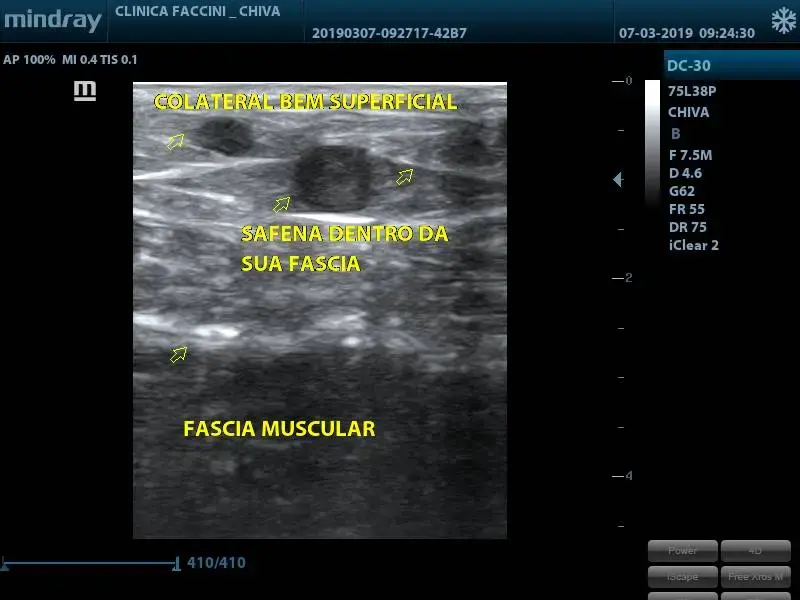

As veias mais profundas tem compartimentos musculares e fascias que impedem o crescimento. As superficiais somente tem gordura e pele que oferecem menos resistencia.

A foto abaixo mostra uma imagem que mostra a posição das diversas veias nas pernas. O video no link Youtube mostra o que acontece com um sistema em equilibrio quando entra um novo ponto de entrada de fluxo nele. Seria o exemplo de uma sistema venoso superficial na perna quando recebe refluxo do sistema venoso profundo por alteração.